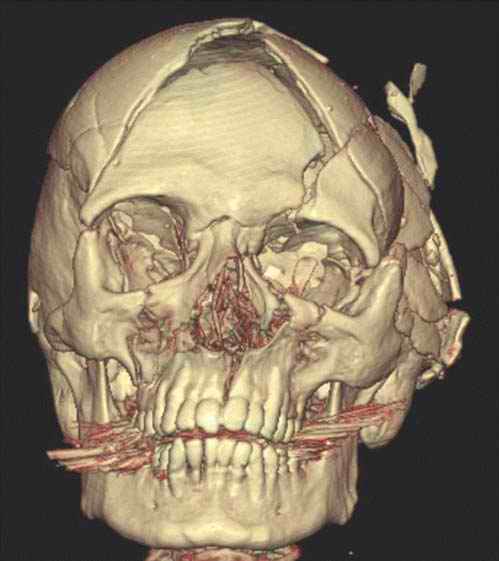

Facial fractures are a common finding in clinical forensic medicine and in forensic pathology. They usually arise due to direct trauma as in vehicle accidents, falls onto the face (often seen in intoxicated persons), or, more frequently, in fights and scuffles.

Of these, the fracture of the nasal skeleton is the most frequently encountered. Although generally a self-limiting lesion with little or no danger to the individuals' life or general health, nasal fractures can lead to the suspicion of an involvement of a third party in otherwise inconspicuous conditions. If an otherwise unharmed body of a young man is found in a locked flat with signs of a nasal fracture, then further investigations must be undertaken, even if the presence of a perpetrator at the time of death can be excluded. As the nasal fracture is a possible sign of a prior fight, an autopsy must be performed to examine the possibility of further, externally unseen lesions. However, a nasal fracture may be missed at external inspection. As a dissection of the face leads to disfigurement, the pathologist often refrains from this procedure. Therefore, the nasal fracture may even be missed after an otherwise complete autopsy has been performed. Postmortem multislice computed tomography (MSCT) easily detects such possibly telltale fractures (Figure D3.2.7).

Other frequently seen fractures of the facial bones concern the eye sockets and can arise due to direct blunt trauma due to punches or impact from a flying object such as a ball. These blow-out fractures are typically located at the medial and basal wall, where the bone is extremely thin [6,7]. However, eye socket fractures can also arise due to indirect trauma, such as in cases of falls with an impact to the back of the head as a contrecoup lesion [8]. Whereas these indirect fractures, typically located at the roof of the eye socket, are formed by a negative pressure in the fossa anterior, the opposite may also give rise to fractures of the orbita ceiling [9]. Such a rapid positive pressure can be achieved by gunshots to the skull.

As is well known from clinical medicine, mid-face fractures can also extend over the maxilla and the zygomatic bone (Figure D3.2.8). These fractures arise from a direct impact to the face. Depending on the involved structures, these fractures are classified as Le Fort I-III. This classification can be difficult, especially in cases of vehicle accidents, where, due to the massive damage, multiple fractures are often seen. In such cases, the Le Fort classes overlap (Figure D3.2.9). Mandibular fractures occur due to punches, falls, and vehicle accidents, to name just a few mechanisms. Direct fractures are seen paramedially, whereas indirect fractures are mostly located in the region of the joint and the mandibular body.

Postmortem imaging can display such possibly telltale injuries in a rapid and nondestructive manner, thus sparing the face from further disfigurement or the pathologist from missing a potentially important finding.